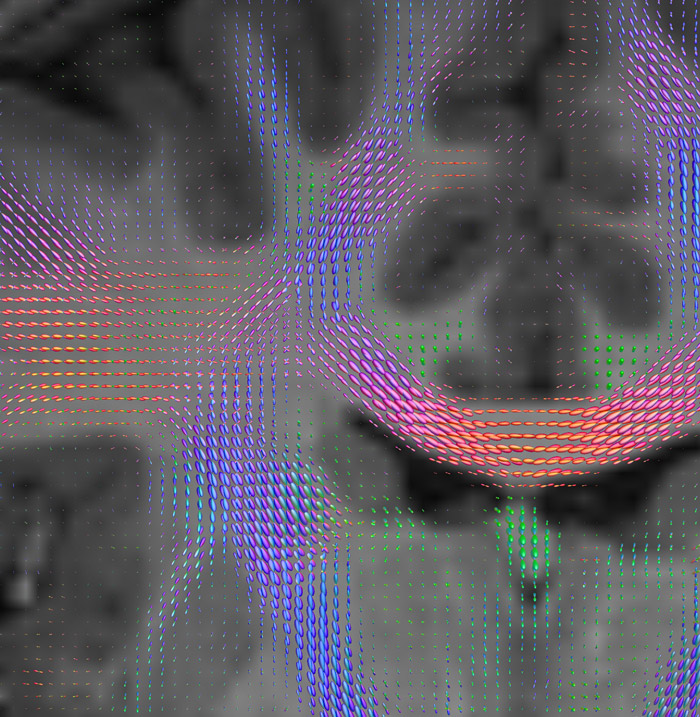

CSD of multishell DWI results in the white matter FOD at each voxel. Unlike the conventional diffusion tensor model, this approach enables accurate modeling of multiple fiber populations within a single voxel.

Crossings of the corpus callosum, corticospinal tracts, and the superior longitudinal fasciculus are shown.

All images were created from the same acquisition in a child using Ingenia 3.0T CX and 32-channel dS Head coil. Diffusion data was acquired at b-values 0, 500, 1000, 2000, 3000. The use of high b-values (3000 s/mm2) effectively suppresses extra-axonal water signal and provides high angular resolution.